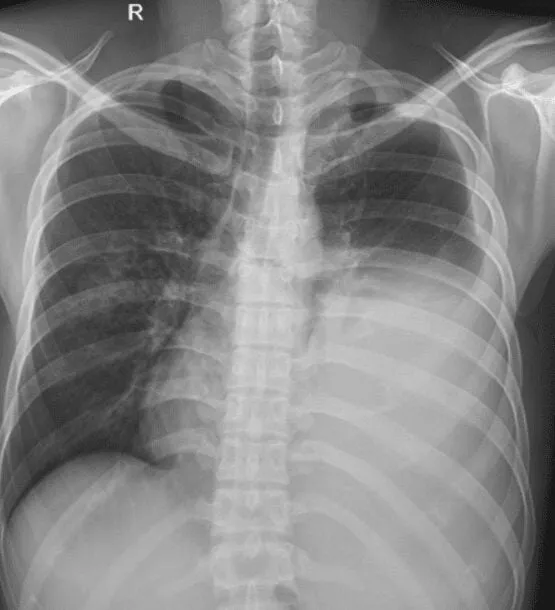

Một số bệnh nhân có các biểu hiện như ho ra đờm, khó thở có thể được bác sĩ chỉ định chụp X-quang phổi. Sau khi chụp, hình ảnh X-quang hiển thị phổi bị màu trắng khiến nhiều người hoang mang không biết bản thân mắc vấn đề gì. Bài viết này, sẽ giúp bạn hiểu rõ hơn phổi bị trắng là bệnh gì và có nguy hiểm hay không.

Chụp X-quang thấy phổi bị trắng nghĩa là gì?

Chụp X-quang phổi là kỹ thuật được dùng nhiều nhất trong tầm soát, phát hiện và chẩn đoán các tổn thương của nhu mô phổi. Phương pháp này sử dụng năng lượng bức xạ từ tia X đi xuyên qua những cơ quan trong lồng ngực để ghi lại hình ảnh. Từ đó, bác sĩ có thể phát hiện các dấu hiệu lâm sàng, tìm ra nguyên nhân gây bệnh và lựa chọn các phương pháp can thiệp phù hợp.

Chụp X-quang thấy phổi bị trắng có thể báo hiệu nhiều vấn đề về phổi, nhưng không có một câu trả lời cụ thể nào vì bác sĩ sẽ cần so sánh các vùng phổi trên, giữa và dưới ở bên trái và bên phải. Nhìn chung, hình ảnh phổi bị trắng cần nhiều sự đánh giá hơn để có thể xác định được vấn đề. Sự bất đối xứng của mật độ phổi được thể hiện dưới dạng độ trắng bất thường hoặc độ đen bất thường trên phim chụp.

Ví dụ, trong trường hợp các tổn thương lấp đầy phế nang (hay còn gọi là dấu hiệu phế quản hơi), hình ảnh X-quang phổi bị trắng có thể có vệt sáng, chia nhánh; thông thường, đây có thể báo hiệu cho tình trạng viêm phổi nhiễm khuẩn (thường chỉ thấy ở giai đoạn đầu), ho máu, phù phổi, v.v. Ngoài ra, một trường hợp khác là nốt đơn độc tại phổi sẽ xuất hiện dưới dạng phổi bị đốm trắng có đường kính nhỏ hơn 3cm; đây có thể do nhiễm trùng phổi, nhiễm nấm, v.v.

Tóm lại, bác sĩ sẽ là người đánh giá và chẩn đoán hình ảnh X-quang phổi bị màu trắng. Hình ảnh này không thể đưa ra câu trả lời chính xác cho việc bạn đang mắc bệnh gì mà còn căn cứ vào nhiều yếu tố khác nhau.